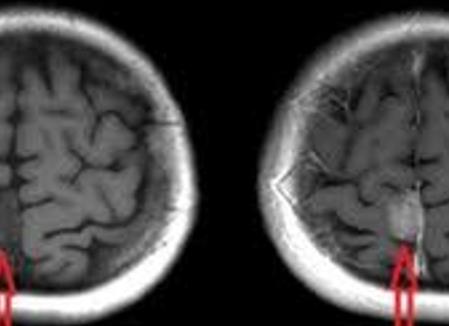

- чёткие, ясные снимки, полученные в разных срезах, возможность компьютерного 3D-моделирования внутренних органов и сосудов;